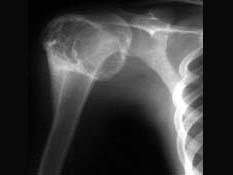

问题 男,29岁,右肩肿物4年,质地硬,压痛不明显,请结合图像,选择最佳答案 ( )

选项 A、巨细胞瘤 B、软骨肉瘤 C、骨转移瘤 D、成软骨细胞瘤 E、结核

答案 D